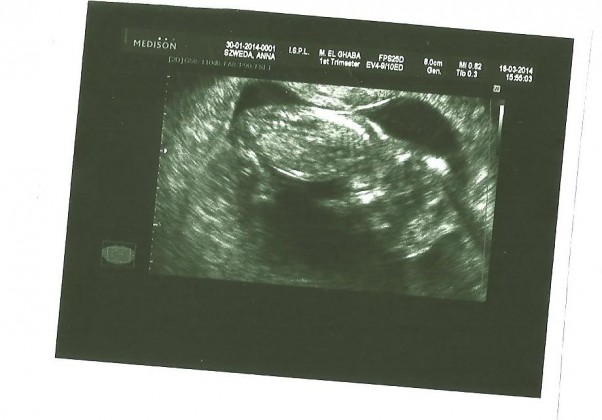

Dziś byłam na kolejnej wizycie kontrolnej. to już 40 tydzień. Mam 3 cm rozwarcia i pojawiły się skurcze. Wprawdzie odczuwałam je już wcześniej ale teraz są silniejsze i nie znikają tak szybko. Chyba rano trzeba będzie się zebrać do szpitala. Pojawiła się tez wydzielina z krwią na bieliźnie po badaniu.

Maluszek urósł - ma 3100 więc jest akurat żeby przyjść na świat. Mam nadzieję, że to nastąpi jutro bo nie chce mi się już dłużej czekać.